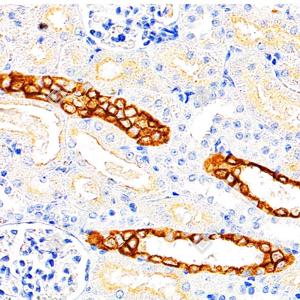

IHC检测Cytokeratin 18蛋白(货号 GB15232). 样品: 大鼠肾, 4%多聚甲醛 (货号G1101) 固定12-24小时. 抗原修复: 柠檬酸抗原修复液(干粉, pH 6.0) (G1201), 高压锅均匀喷气计时2分钟. —抗: 1: 500稀释, 4℃ 孵育过夜. 二抗: S-vision免疫组化多聚二抗(山羊抗小鼠), 即用型(货号G1301), 室温孵育20分钟. |